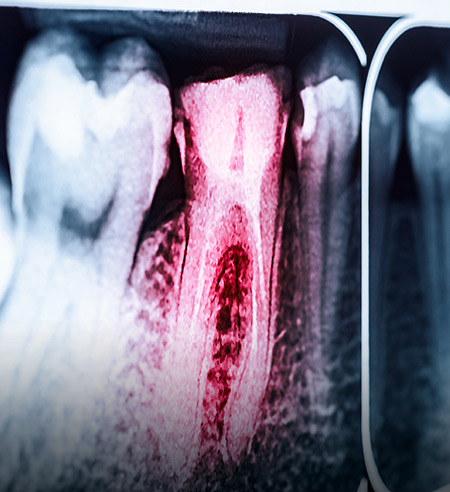

Root Canal Treatment

Root Canal Treatment | Lara Village Dental